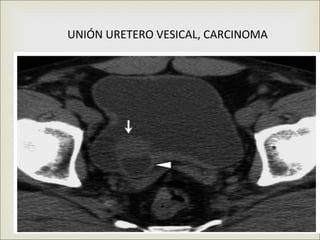

UNIÓN URETERO VESICAL, CARCINOMA

URO-TAC   Es la tomografía no contrastada con énfasis en el tracto urinario (uro-TAC).  Permite realizar un diagnóstico de obstrucción en cualquier segmento del tracto urinario con alta especificidad y sensibilidad.

Utilidad • Alteraciones de las vías renales  • CA renal • calculo • Infección renal • gas en las vías urinarias • Hemorragia • edema renal • masas inflamatorias • obstrucción